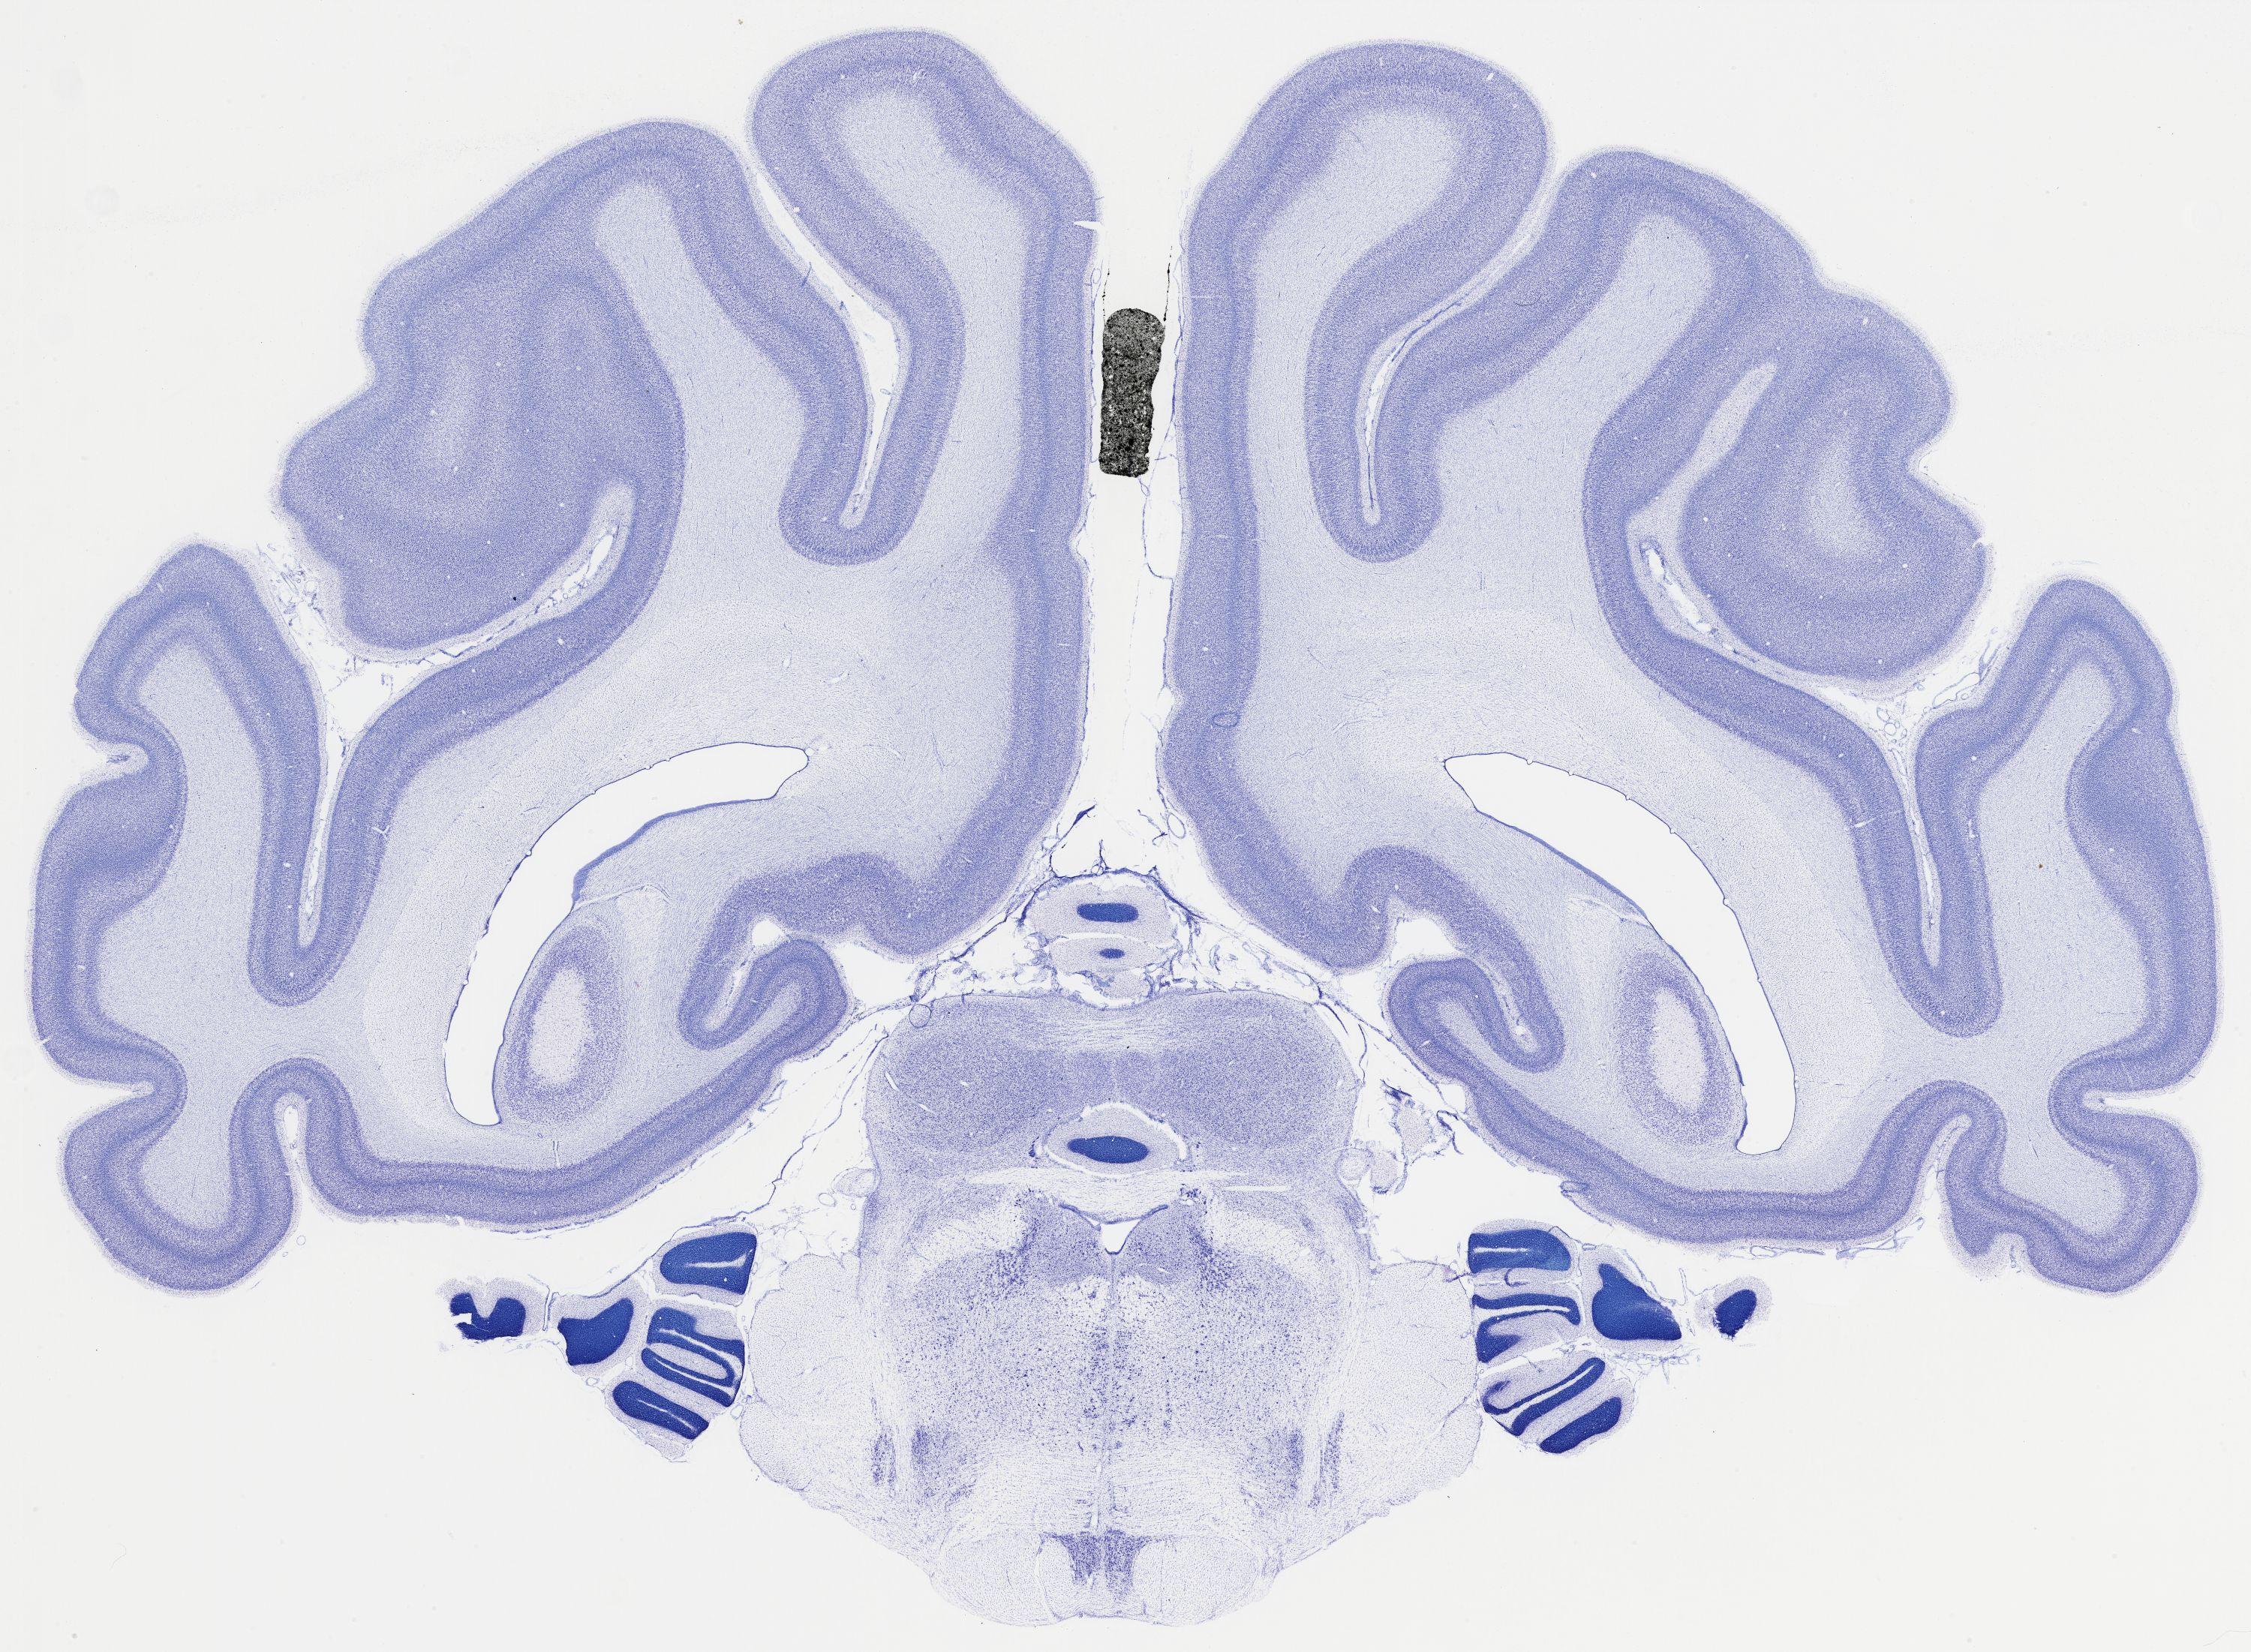

Datasets -> Chlorocebus Aethiops -> Nissl, coronal, histo, Whole-Brain, adult

[ Metadata ]   ·   Source: NeuroScience Associates

thumbnail

523